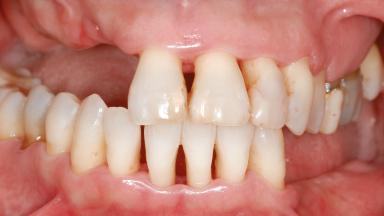

A 46-year-old woman was referred for treatment whose main complaints were mobility of her fixed partial dentures (right maxilla and left mandible) and periodontal bleeding during function. She also reported having taken systemic antibiotics to treat recurrent swelling in the area of the upper left molars. The patient had not seen a dentist for at least 2 years. She did not smoke and had no history of major systemic disease other than two minor orthopedic procedures some years back. The first-visit examination revealed poor plaque control, tooth mobility, periodontal disease, and a residual dentition widely associated with deep periodontal pockets.

| Soft Tissue Contour and Volume | Significantly deficient |